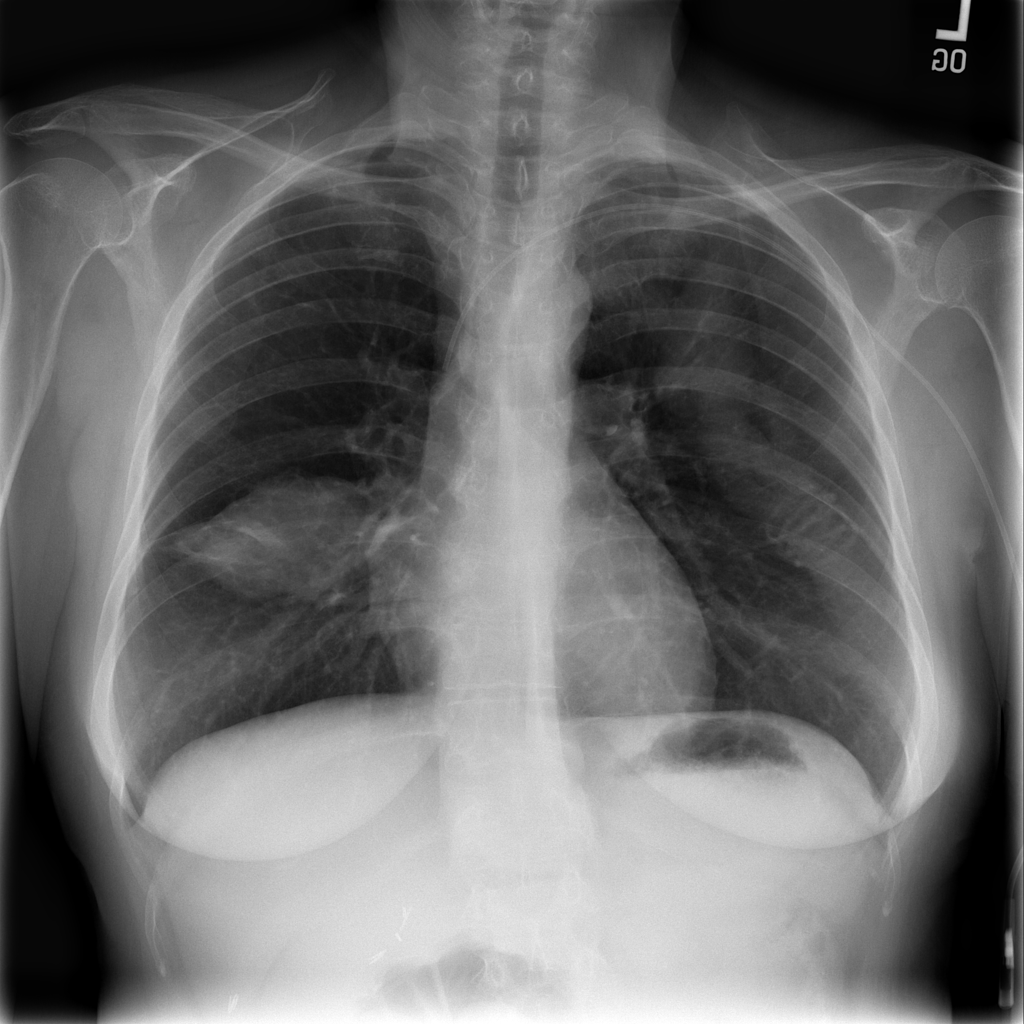

Mass

A mass is a larger focal opacity or lesion seen on the image. It is a descriptive finding that can have several causes and usually needs more imaging or clinical context to characterize.

PAT-C0E5 · IMG-001Mass

PAT-C0E5 · IMG-001

PA